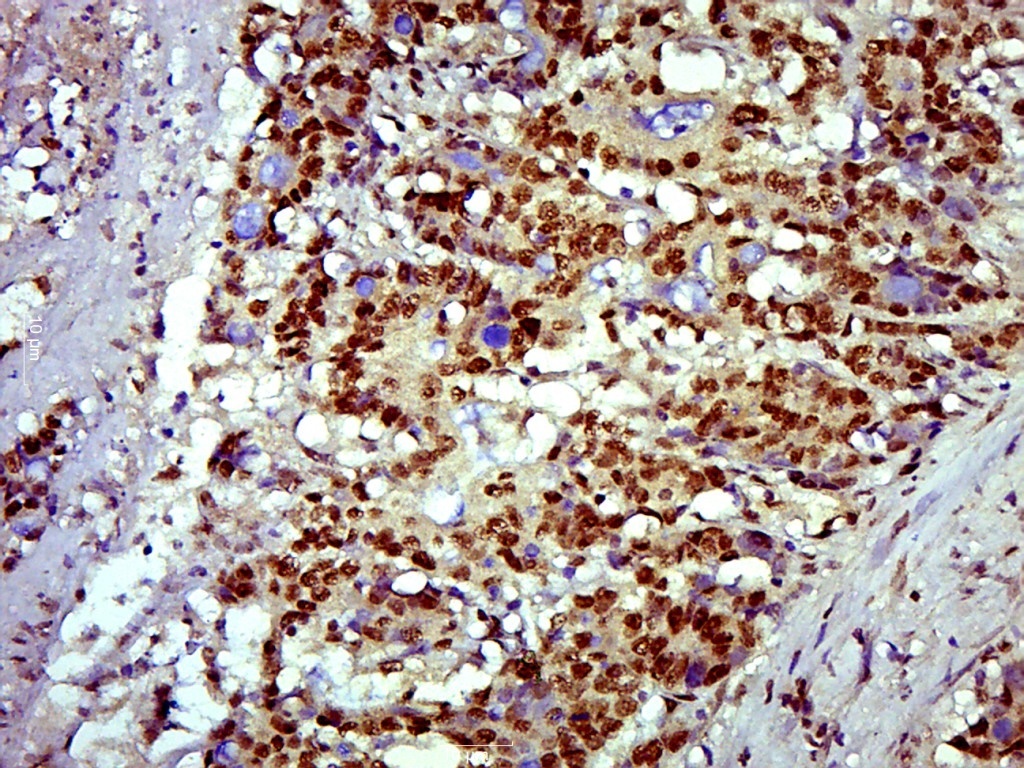

| 产品应用 | IHC-P=1:100-500, IHC-F=1:100-500, IF=1:100-500, Flow-Cyt=1ug/test Not yet tested in other applications. |

| {IHC-P} | {1:100-500} |

Primary Antibody (green line): Rabbit Anti- SOX9 antibody (bs-4177R),dilution: 1μg /10^6 cells;

Isotype Control Antibody (orange line): Rabbit IgG .

Secondary Antibody (white blue line): Goat anti-rabbit IgG-PE,Dilution: 1μg /test.